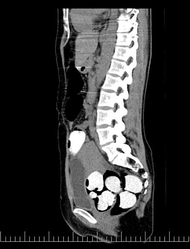

Dva muži ve věku 36 a 60 let dorazili s třiatřicetiletou ženou do Prahy již před deseti dny. Cestovali z Ekvádoru přes Madrid. "Polykače celníci odhalili na základě jejich chování a informací o průběhu cesty. Prvotní podezření na pašování drog jim potvrdilo následné rentgenové vyšetření," uvedla mluvčí Generálního ředitelství cel Martina Kaňková.

Podezřelou trojici umístili policisté do nemocnice, kde sledovali jejich vylučování pomocí speciálního WC. V úterý odpoledne prý zaznamenali poslední ze 134 gumových kapslí s kokainem podobných prezervativu.

Trojice měla v trávicím traktu podle policie celkem zhruba pět kilogramů drogy, přičemž mužům putovalo střevy až 55 kapslí, žena jich spolykala 23. Podle Kaňkové byl kokain rozpuštěný ve speciálním roztoku, ze kterého lze drogu získat zpět v podobě prášku. Pro celníky je podle jejích slov případ výjimečný také průměrným množstvím drogy na jednu kapsli: zatímco obvykle je to do deseti gramů, v tomto případě navážili 38.

Celníci zadrželi tři pašeráky na základě jejich podezřelého chování (ilustrační foto).